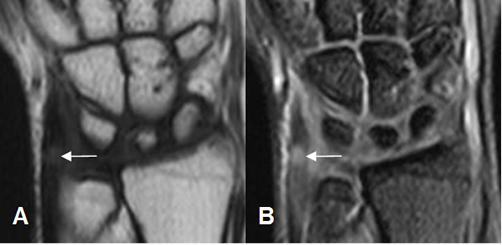

En la RM, los hallazgos son similares a la ecografía. Engrosamiento del tendón y alteración de su SI por tendinitis y presencia de liquido a su alrededor, por tenosinovitis. (Fig 90 a 93).

Fig 92. Tenosinovitis.

A: RM axial en T2 y B: RM coronal en STIR. Tendón del flexor radial del carpo rodeado por líquido, secundario a tenosinovitis.